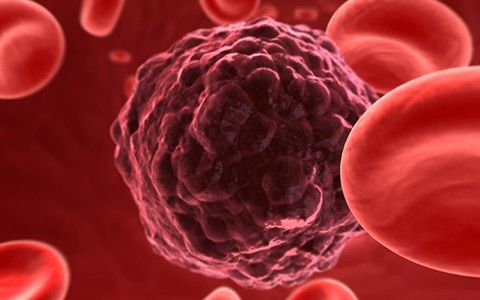

Oncology is a stream in medicine which mainly deals with the prevention, diagnosis, and treatment of cancer. The medical expert who practices oncology is said to be an oncologist. Oncology is the study of cancer (tumor). Usually, an oncologist manages a person's care and treatment once he or she is diagnosed with cancer. The field of oncology has three major areas: medical, surgical, and radiation. A medical oncologist treats cancer using chemotherapy or other medications, for instance targeted therapy.